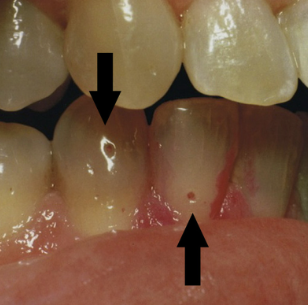

Lichenoid Contact Reaction amalgam (半抗原) LP,但只出現在有 amalgam 的位置、移除 amalgam 即消失。

Lichenoid Drug Reaction 藥物 非直接性 IgG 螢光染色 → string of pearls (沿著複層鱗狀上皮的 basal cell layer 細胞膜) alt text